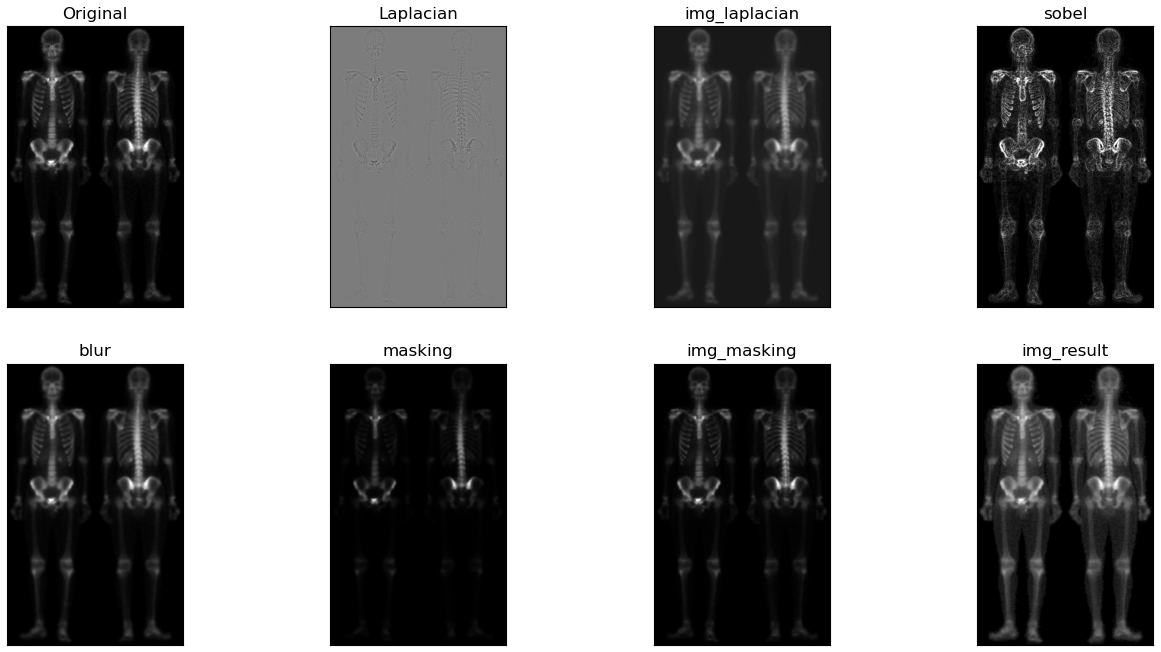

根据上图可知,首先通过对原图像img做拉普拉斯算子运算增强突出图像细节,接着将图laplacian与img图像叠加得到图img_laplacian。又因为二阶求导的拉普拉斯算子也会使得图像的噪声增强,而一阶求导的Sobel算子对噪声和小细节的响应较弱。所以通过对原图像img做X和Y两个维度的Sobel算子运算并相加得到图Sobel。进一步可以对图Sobel进行双边滤波,平滑噪声并保留细节,得到图Blur。然后将平滑后的图Blur和图img_laplacian相乘,乘积可以保留灰度变化强烈区域的细节,同时降低灰度变化相对平坦区域的噪声。最后将结果叠加在原图img,并做灰度图幂变化扩展灰度图范围即可得到最终混合增强的锐化图像。

| 对图像做拉普拉斯运算(需要注意后面运算得到的图像需要将其灰度值映射到0-255范围内) |

| 将其叠加在原图像上,可以略微观察出骨骼细节的增加 |

| 对原图像做Sobel运算,增强了细小的细节,但是噪声也被增加了。 |

| 对Sobel运算得到的图像进行双边滤波,可以平滑噪声保留边界;在书中利用的为均值滤波,我认为此处由于灰度范围比较窄,实际我也使用了均值滤波进行对比,实际差距不大。但是我觉得运用双边滤波会更好一些。 |

| 将滤波后的图sobel与图img_laplacian进行相乘,保留变化强烈的细节,平滑噪声 |

| 将相乘得到的图masking叠加到原图上 |

| 由于图像灰度范围窄,整体偏暗,在此使用灰度幂变换扩展灰度范围,使得更符合人眼观察。 |

γ=0.5,c=1,最终得到的混合增强图像如下,可以看出人体的外形轮廓清晰,手腕,手掌等骨骼细节由人眼也可观察到。

| 最终将各结果进行对比显示 |